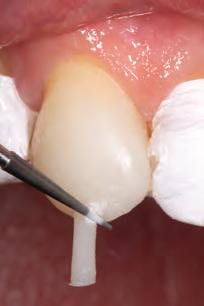

Direct technique with customized prefabricated palatal guides: This technique requires pre-operative impressions of both arches using polyvinyl siloxane (PVS) to prepare a dental cast and transfer the proposed changes from the wax-up.4 (Fig. 5) The palatal index, which is an impression of the palatal portion of the tooth or teeth to be restored, is created using a PVS impression material21 or laboratory silicone.4 During the restorative phase, the index is seated on the palatal side after placing the adhesive. The composite is placed onto the silicone guide to form the restoration’s palatal aspect (palatal/proximal contour and incisal edge).9,10 Once this palatal increment is light-cured, the silicone matrix is removed, and the remaining part of the restoration can be incrementally built up with resin composite.21 A monochromatic material can be used to build the remaining of the restoration, or it can be incrementally built with various opacities and chromaticities to imitate dentin and enamel using “dentin- and enamel-like” materials or by adding layers of translucent composite between the lobes.10 Ultimately, each patient is unique when it comes to selecting the right enamel shade for the final layer.6,10

Advantages of this technique include minimal finishing and polishing of the palatal portion and occlusal adjustments because all details were worked out during the wax-up phase before the matrix fabrication.4,32 The first palatal increment provides a canvas where the dentist can add

the remaining increments to build the restoration.4,10 This technique is beneficial when multiple restorations are to be placed and when the length of the teeth is going to be increased. Thus, the anterior guidance is dialled in the waxup.4,32 Disadvantages include an additional or a longer appointment for impression and laboratory work waxing for future restoration or restorations.32 A longer appointment is required if a polychromatic restoration is to be placed.10 This technique still relies on the ability and skill of the dentist to layer composite and to properly replicate anatomical contours as contouring and polishing.9,10

Fig. 5a: The patient was unhappy about the appearance of her smile due to a Bolton discrepancy. Patient desires to have a beautiful smile.

Fig. 5b: Use palatal matrix with the proposed changes transferred from the wax-up.

Fig. 5c: Palatal contours built over the palatal matrix.

Fig. 5d: Post-operative results after restoration.